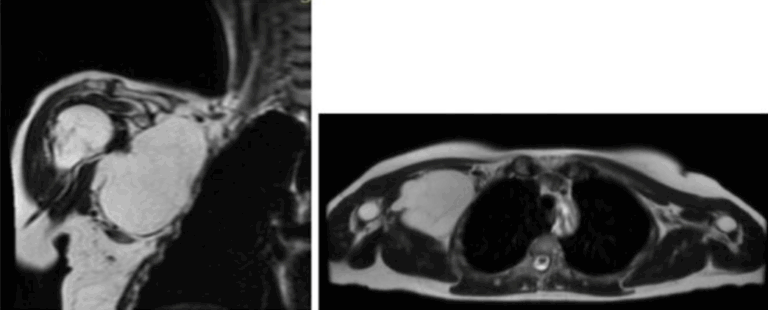

Arthroscopic Single-Layer Hyaluronate-Based Scaffold for Osteochondritis Dissecans of the Glenoid – Copy

Alessandro Donà | Giuseppe Porcellini | Valentina Passarino | Alberto Brigo | Andrea Giorgini | Gian Mario Micheloni | Rocco Bonfatti | Luigi Tarallo IntroductionLipomas